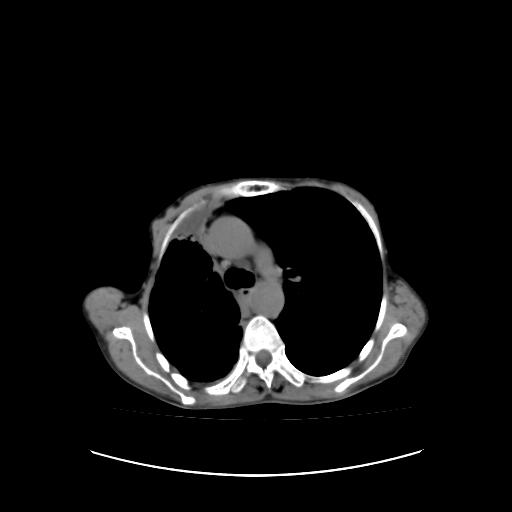

符合:恶性胸水的表现。多考虑恶性胸膜间皮瘤。

右侧胸廓塌陷,右侧胸膜广泛增厚并见多发胸膜结节,右侧少量胸腔积液并包裹。

右侧广泛胸膜增厚,局部呈结节状增厚,右侧胸腔少量积液。双肺未见确切肿块影。纵隔未见淋巴结肿大。气管、支气管通畅。考虑右侧胸膜间皮瘤(恶性?)可能性大。支持!

右侧恶性胸膜间皮瘤可能性大。